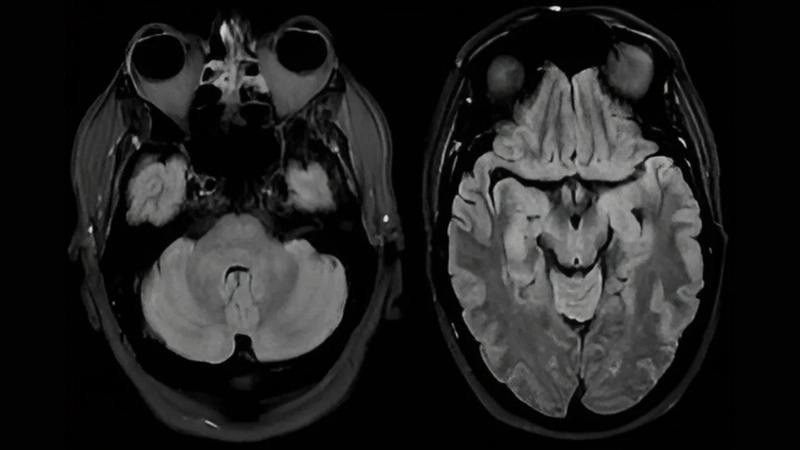

Image description of Powassan Encephalitis

Powassan Encephalitis is a rare, tick-borne viral infection that affects the brain. It can cause fever, headache, and severe neurological complications if left untreated.